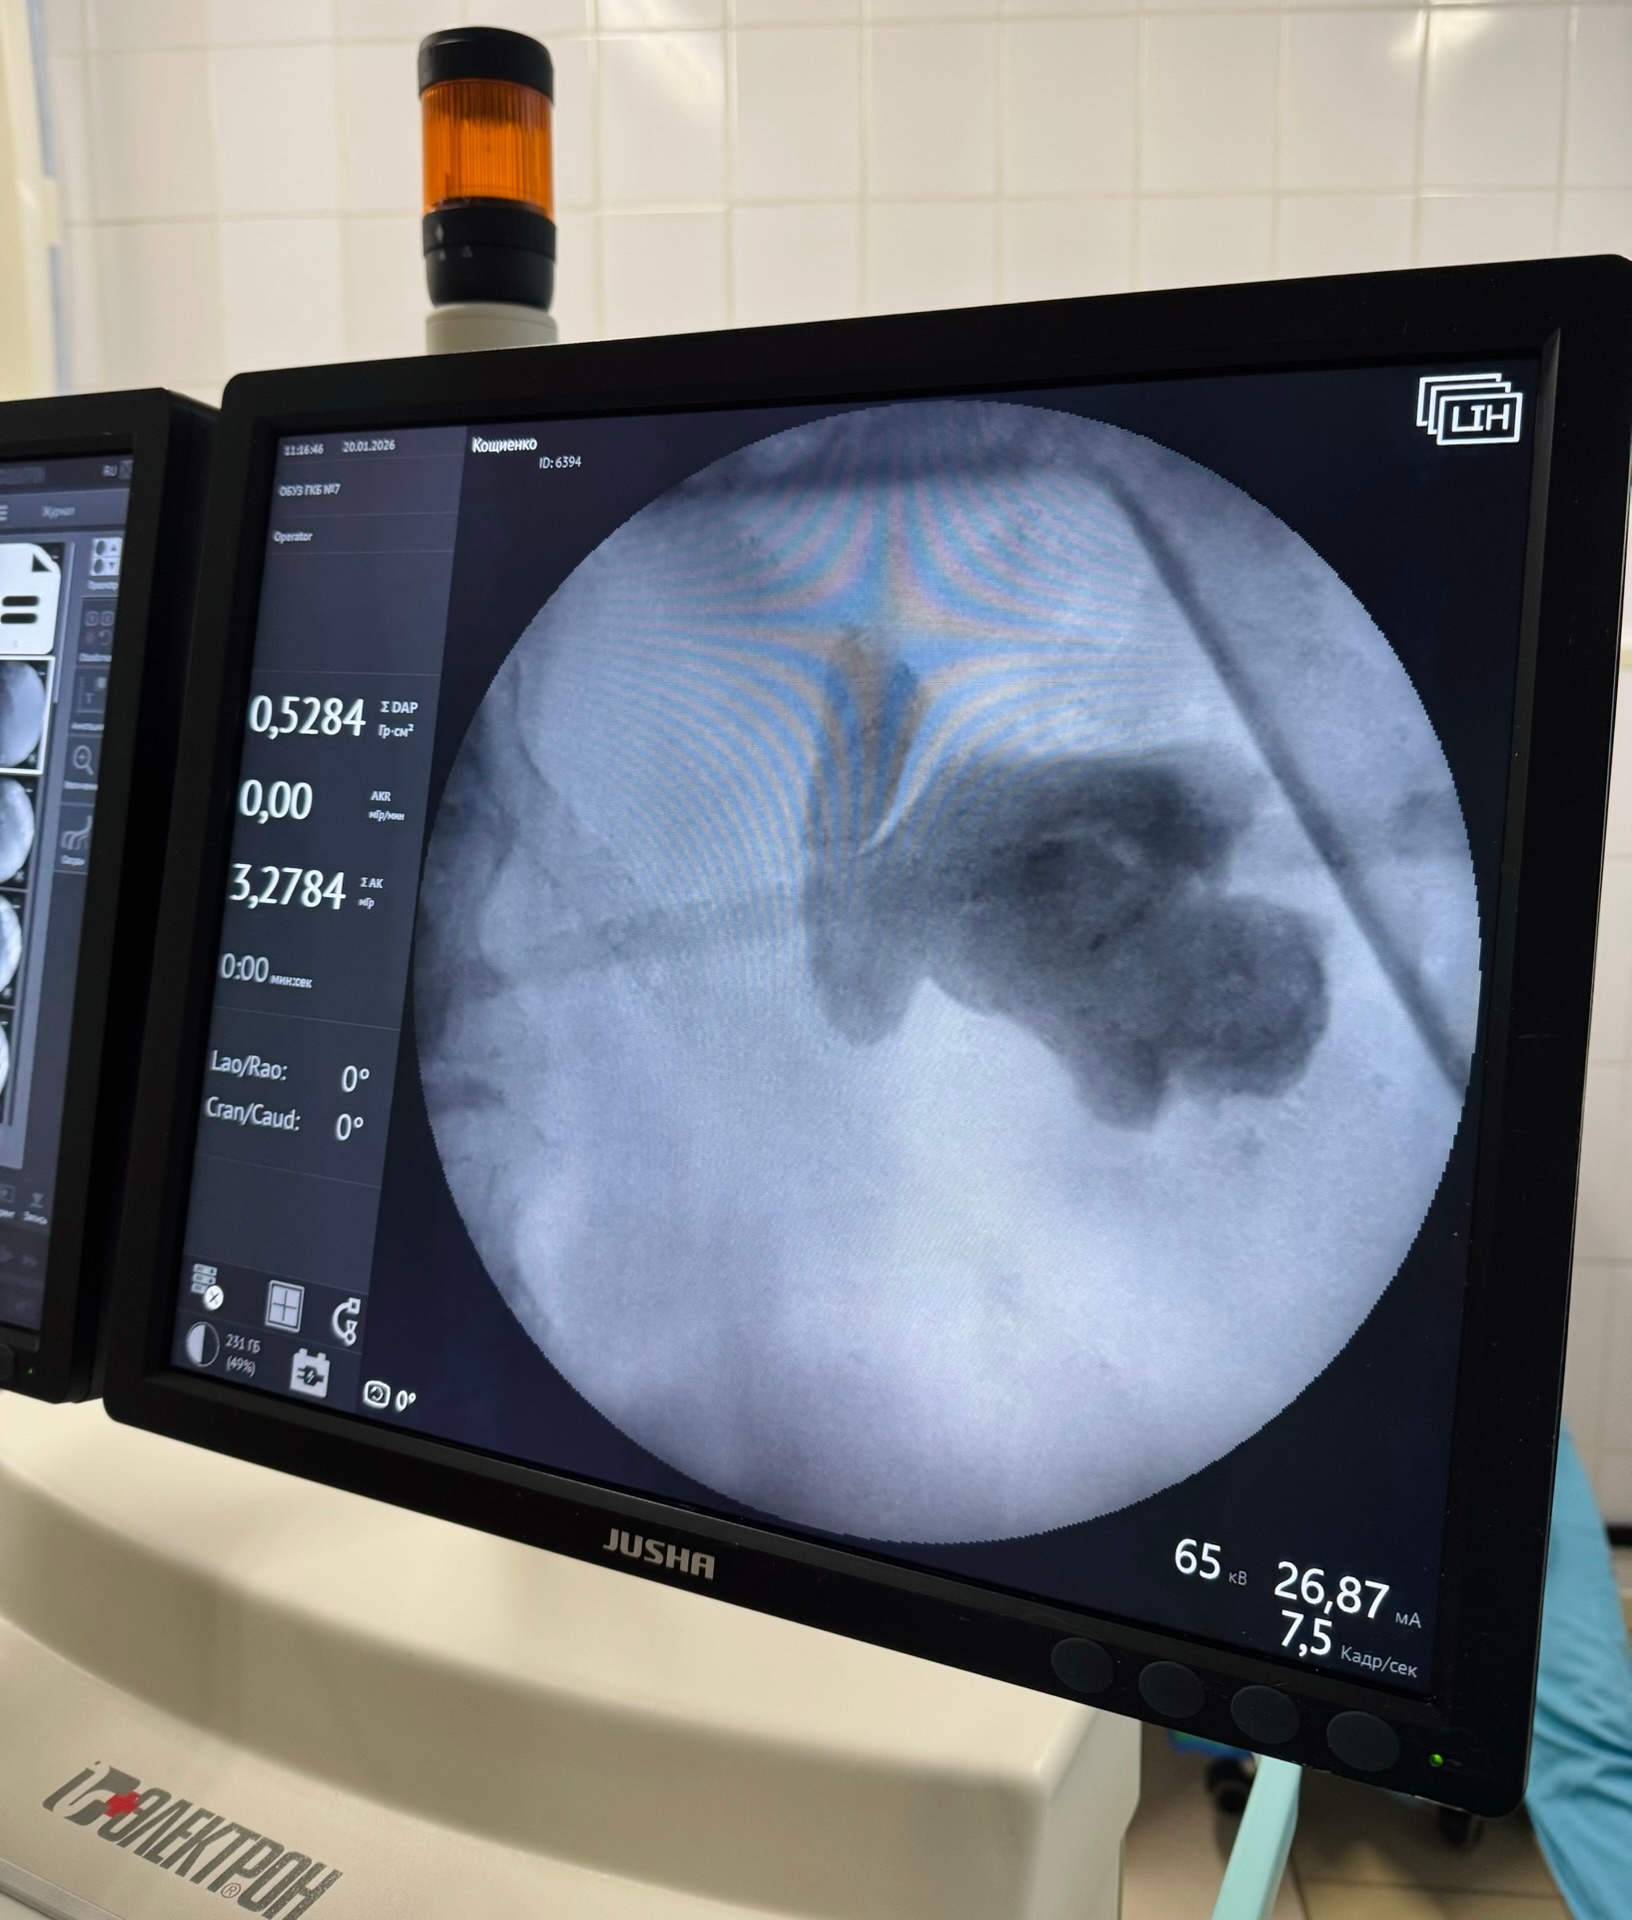

Недавно в практике врачей произошёл случай, который потребовал высокого профессионализма и применения современных технологий. У женщины обнаружили коралловидный камень в почке (по классификации К-4), который полностью заполнил чашечно-лоханочную систему. Это максимальный размер конкремента, возможный для человеческого организма. Ситуация усложнялась тем, что у пациентки была единственная почка, а один из фрагментов камня переместился в среднюю треть мочеточника, заблокировав отток мочи.

Учитывая сложность ситуации, было принято решение о проведении комбинированной операции малоинвазивными методами. Врачи одновременно раздробили лазером камень в мочеточнике через естественные мочевые пути и раздробили и удалили его из почки через небольшой прокол в пояснице с применением энергии гольмиевого лазера и ультразвукового литотриптера.